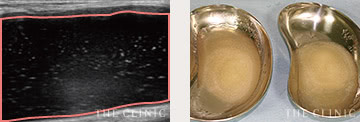

除去したヒアルロン酸   目視することで確実に除去

しこりの状態で処置を判断

ヒアルロン酸豊胸のしこりの除去方法は、しこりの状態によって異なります。通常なら、ヒアルロン酸溶解液のヒアルロンダーゼを注射することで、解決できます。瘢痕化したしこりは切開する必要がありますが、多くのケースはバストにメスを入れなくても、しこりの除去が可能です。

ヒアルロニダーゼという加水分解酵素を、ヒアルロン酸豊胸のしこりに注入する方法です。ヒアルロン酸を溶かすことで、吸収されやすい状態にすることが可能。これを注射器で吸引することで、より確実に除去できます。